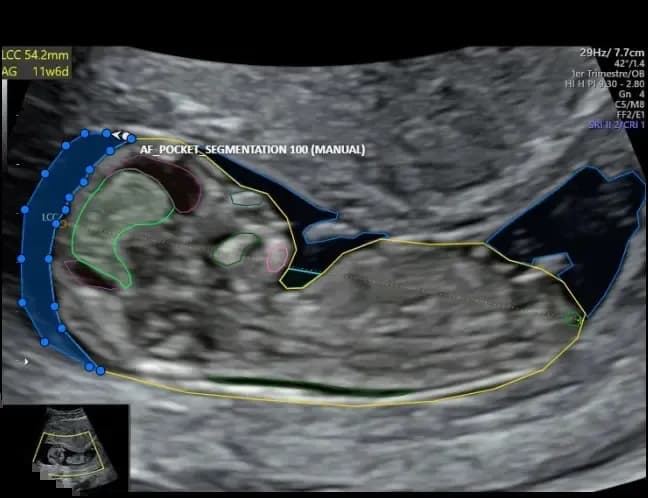

We enable healthcare providers to extract insights from patient records, streamline documentation, and deploy virtual assistants to enhance patient engagement.